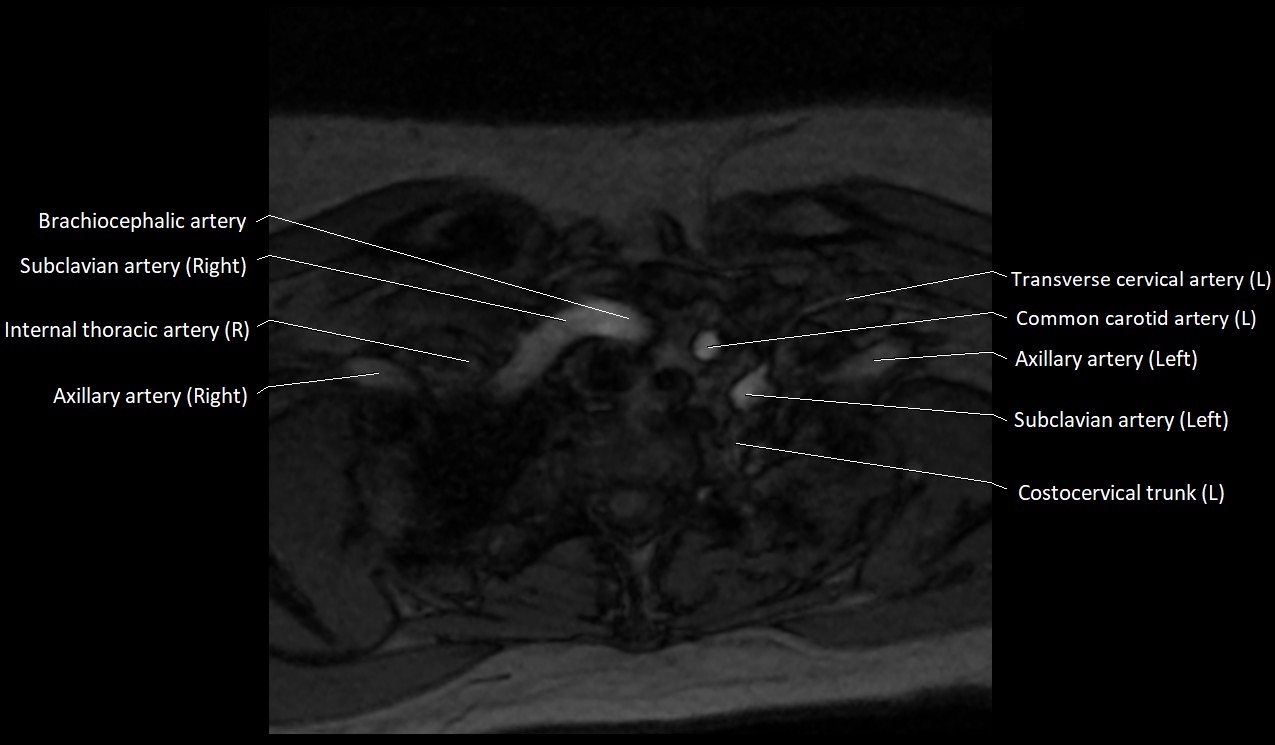

CT image

image